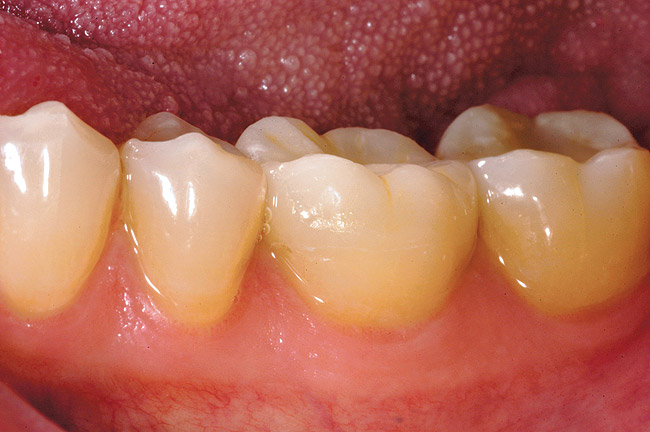

A chamfer finish line provides for the most esthetic blending of porcelain and tooth structure and is commonly added as the final detail to the facial aspect of the preparation (Figure 5). The occluso-cervical position of the facial chamfer is largely dependent on the need to alter tooth color. If the inherent color of the tooth is acceptable, a 2-mm chamfer is all that is required to blend the porcelain/tooth interface (Figure 6A through Figure 6E). A need to effect a color change dictates a facial finish line carried to the free gingival margin.

Figure 6a  A patient presents with a fractured mesiolingual cusp, a large amalgam restoration, and a crack line across the distal marginal ridge on tooth No. 19. Note only a thin rim of enamel remains at the site of fracture.

Figure 6a

Figure 6b  Tooth No. 19 is compromised axially on the mesiolingual, but a great deal of structural integrity still remains on the facial aspect of the tooth. The tooth is prepared for an adhesively retained restoration.

Figure 6b

Figure 6c  The final restoration addresses the occlusal, proximal, and lingual compromises of the tooth yet preserves facial tooth structure.

Figure 6c

Figure 6d  The butt margin on the lingual aspect of the tooth provides an anatomical guide for the ceramist and facilitates restoration of original tooth contours.

Figure 6d

Figure 6e  A 2 mm facial chamfer provides an acceptable framework in which to optically blend the tooth/ceramic interface.

Figure 6e